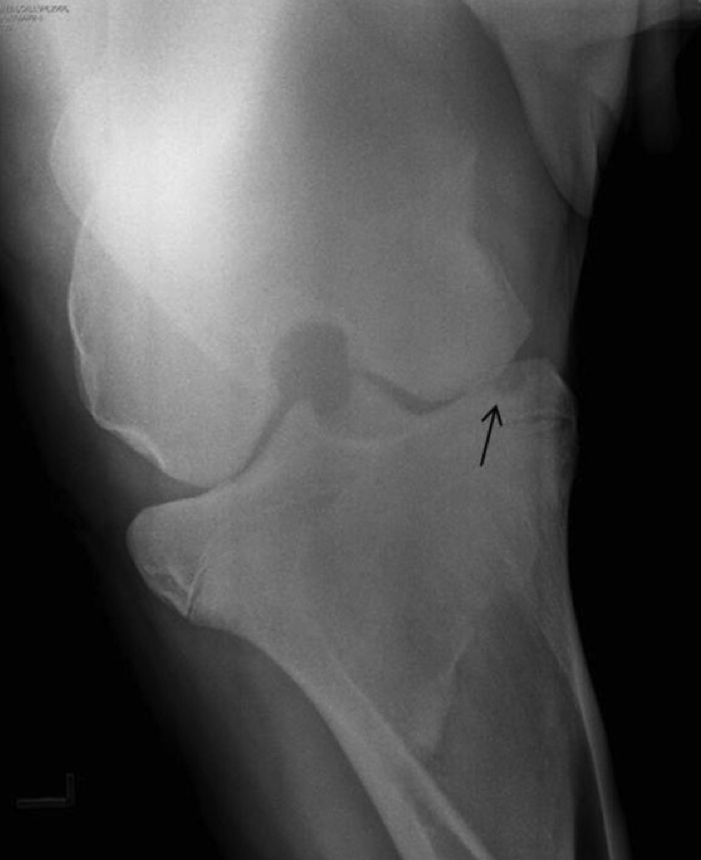

what is the arrow pointing to?

A

subchondral bone cyst